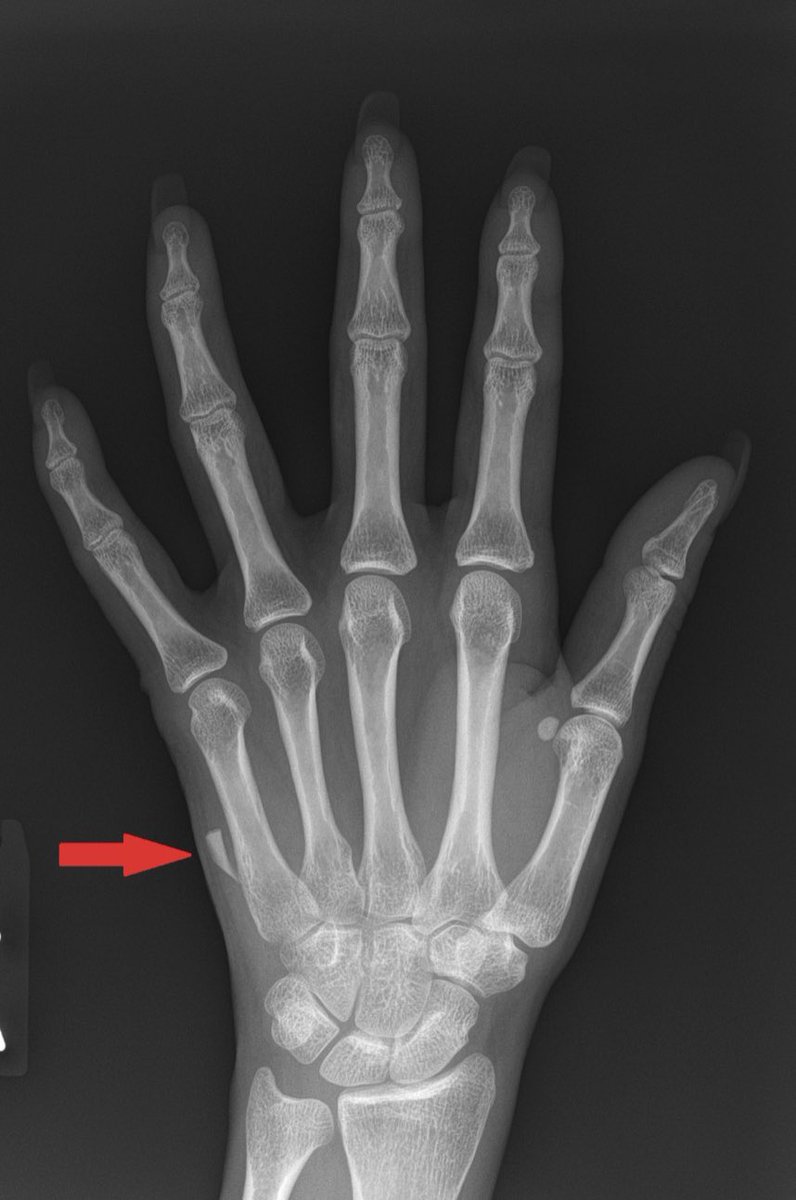

3- الاجسام الغريبة (foreign body):

ممكن يدخل الجرح اجسام مثل الزجاج او اي شيء آخر و غالباً نقوم بعمل اشعة عادية (x-ray) اذا كان فيه زجاج ممكن يبان بنسبة 95% والباقي اننا نشوف الجرح كويس قبل ما نقفله ونوقف النزيف ونتأكد إن مافيه شيء داخل عشان ما يصير التهاب في المنطقة.